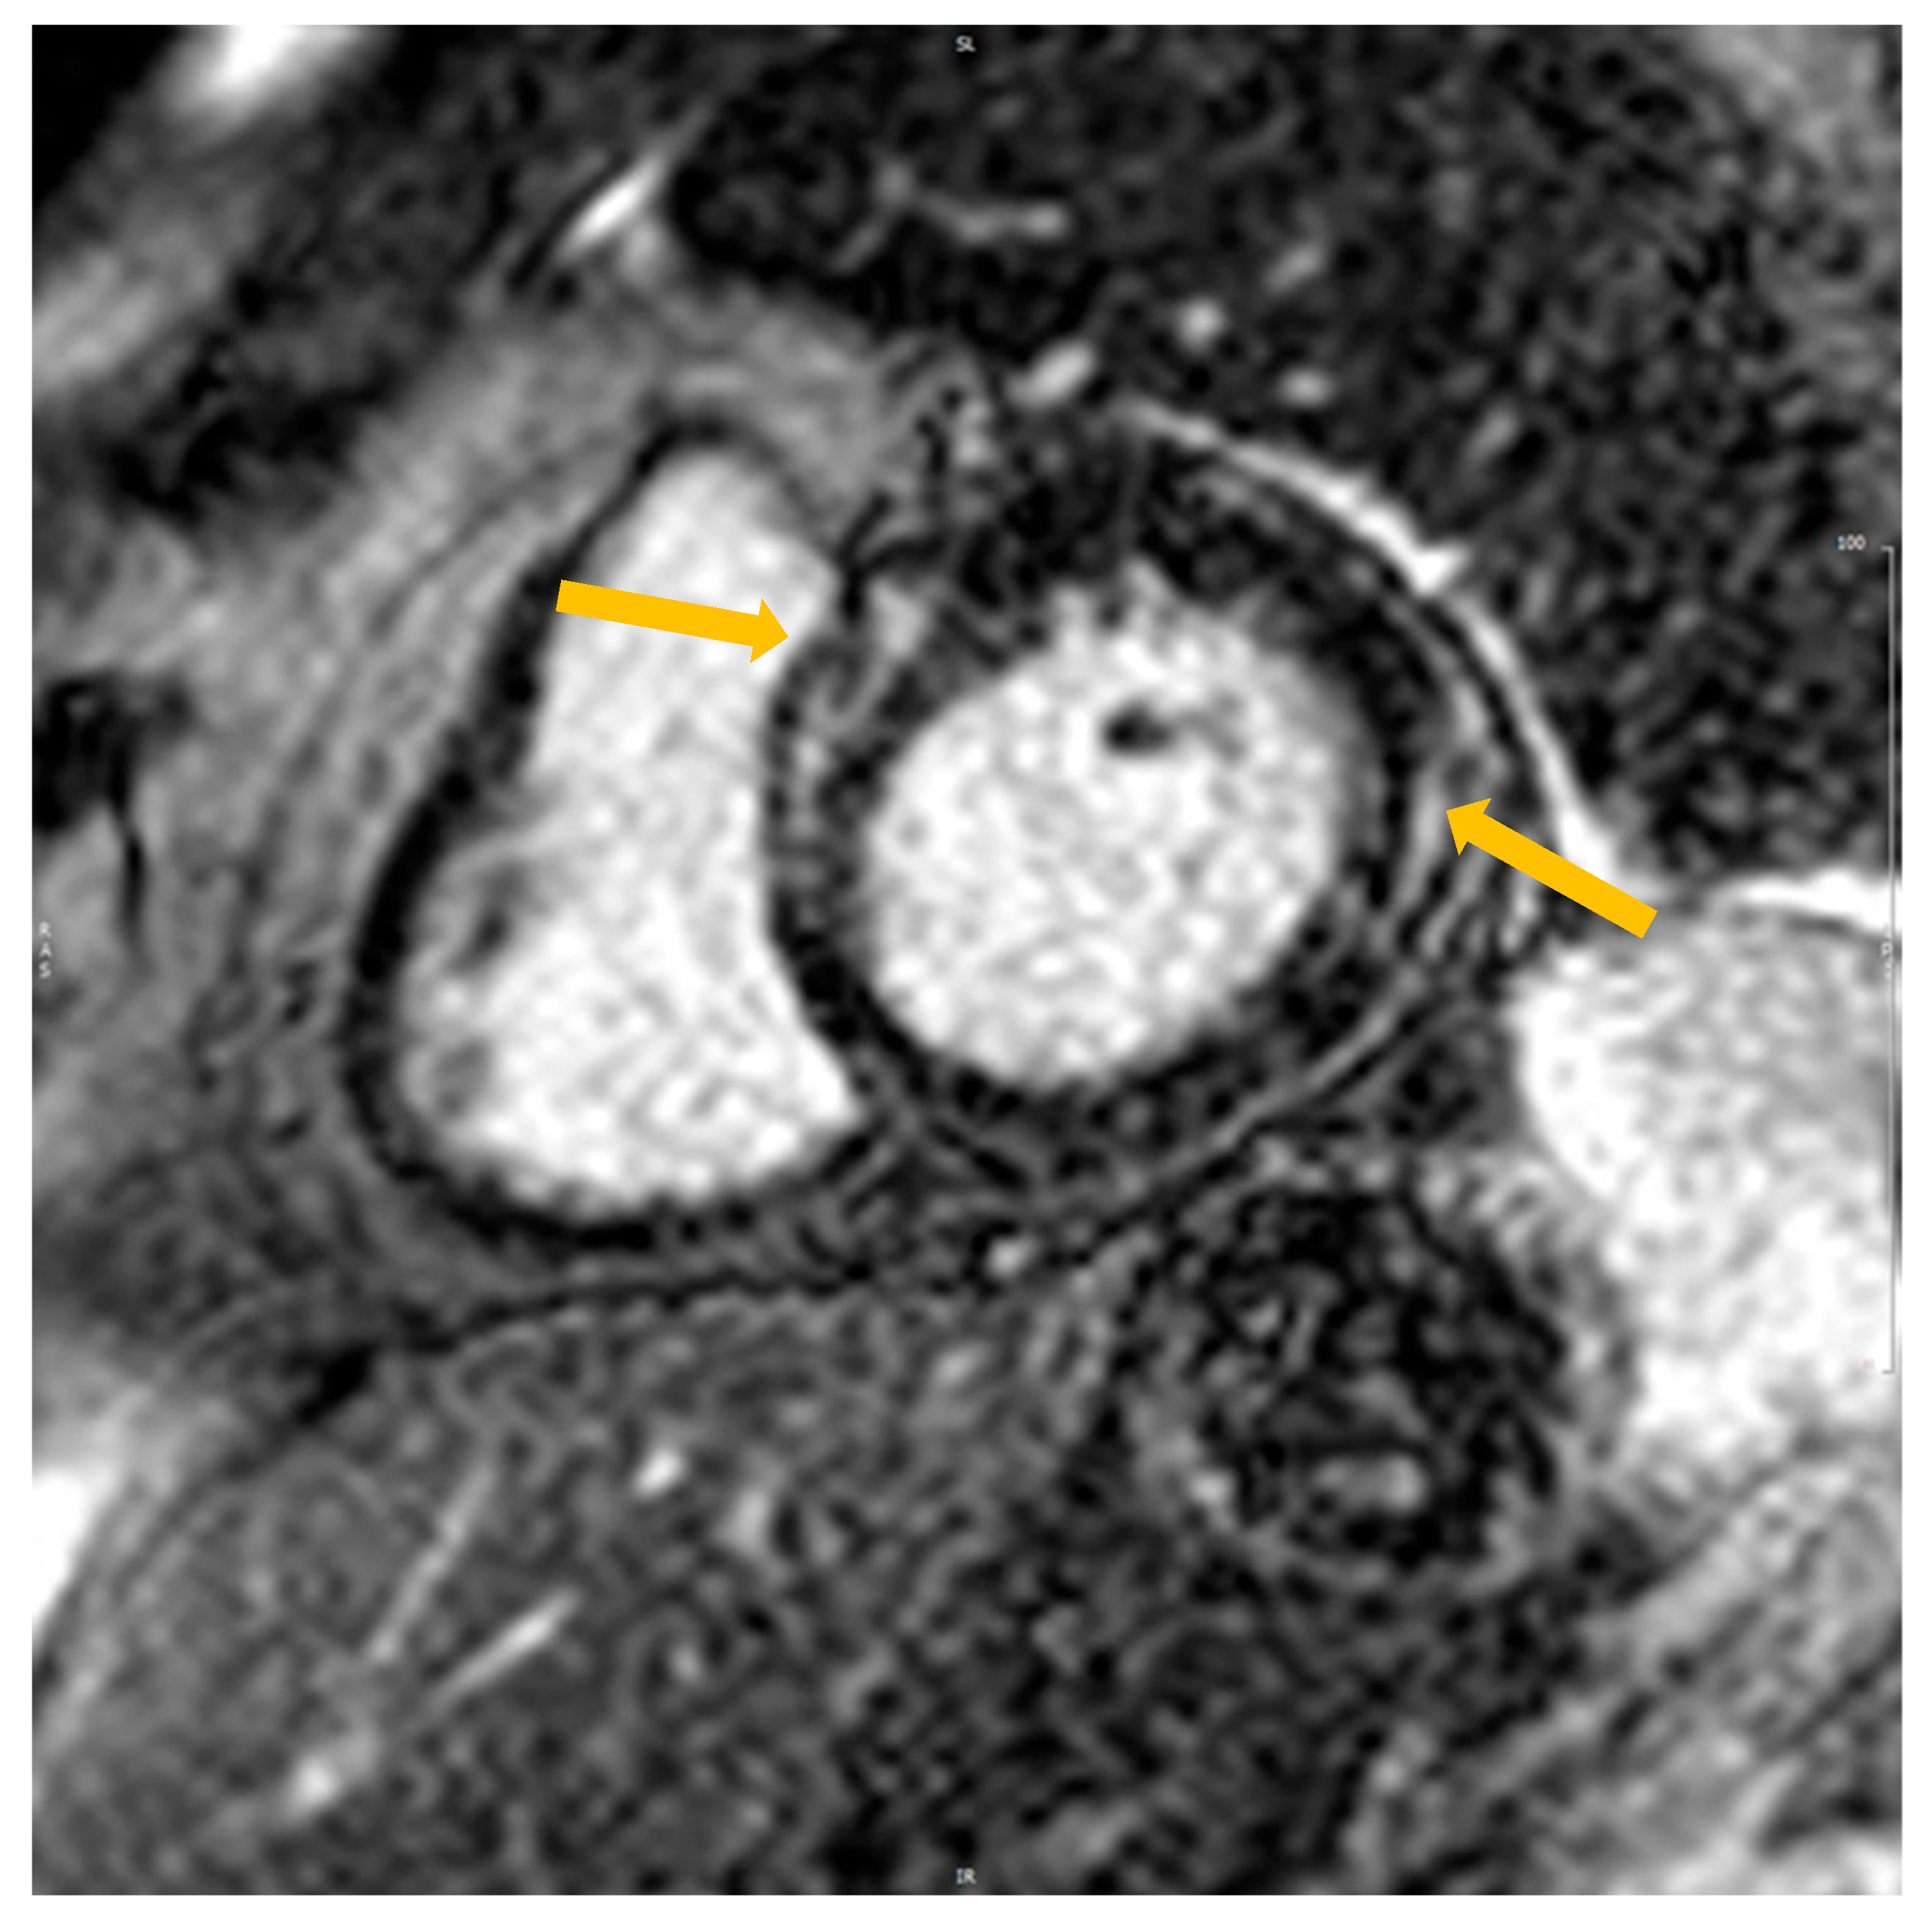

The presence or absence of LGE was determined by reviewing all short- and long-axis contrast-enhanced images (left ventricular outflow tract, short-axis view from base to apex, long-axis, and four-chamber views). Regions of elevated signal intensity were confirmed in two spatial orientations (Figure 1). The data were calculated by one expert (EP). The amount of fibrosis was assessed manually using the ratio of the mass of fibrosis to the total mass of the myocardium.

Figure 1. Cardiovascular magnetic imaging with LGE in the short axis in patients fulfilling the criteria of TIC after DC cardioversion. Yellow arrows—the accumulation of LGE.